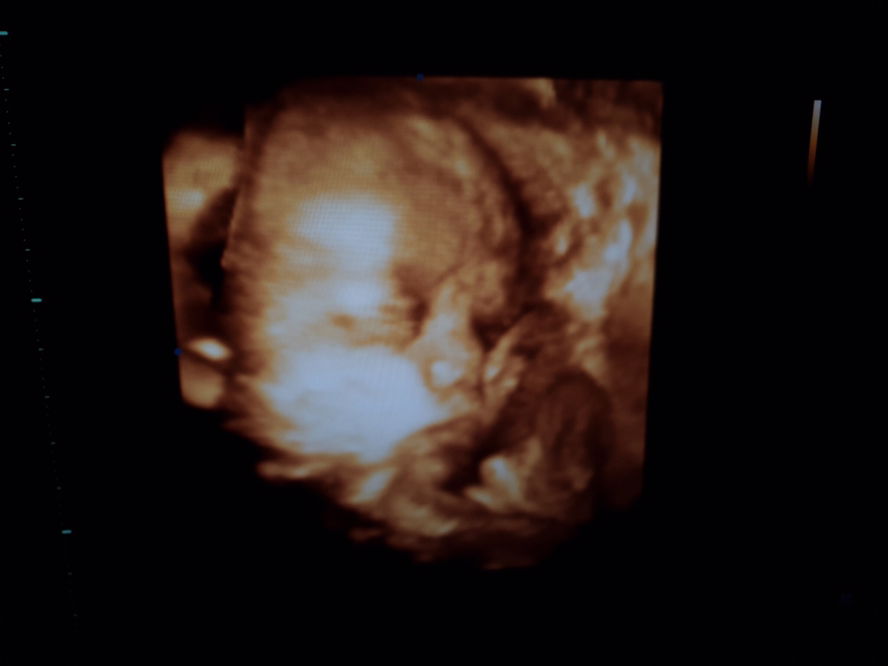

อัลตร้าซาวด์

สวัสดีครับผม31สัปดาห์แล้วครับของแม่ๆกี่สัปดาห์กันแล้วค่ะ ตื่นเต้นมากๆพอใกล้ถึงเวลา #คนแปลกหน้าที่อยากเจอ?? เพศชายครับผม